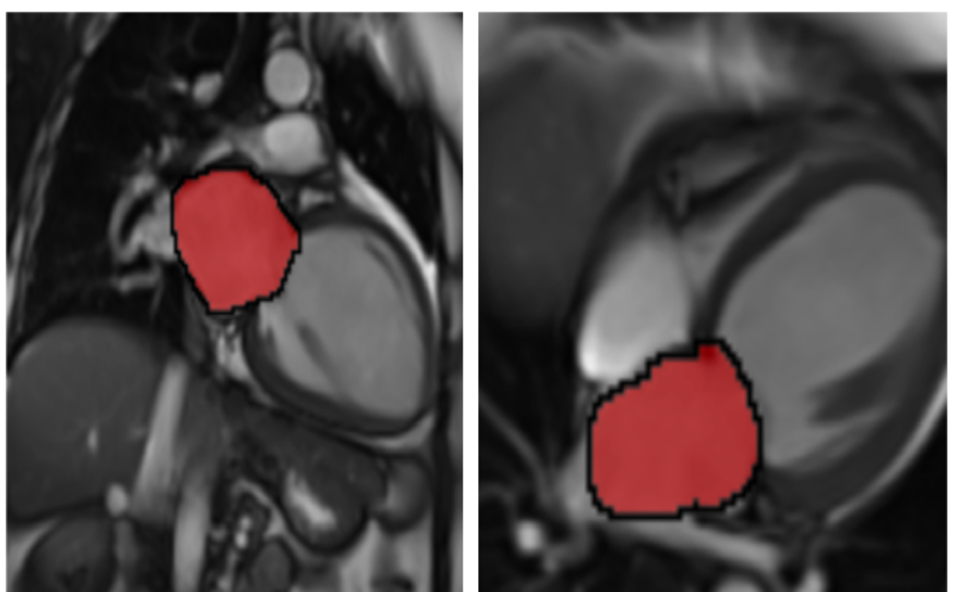

Left atrium assessment